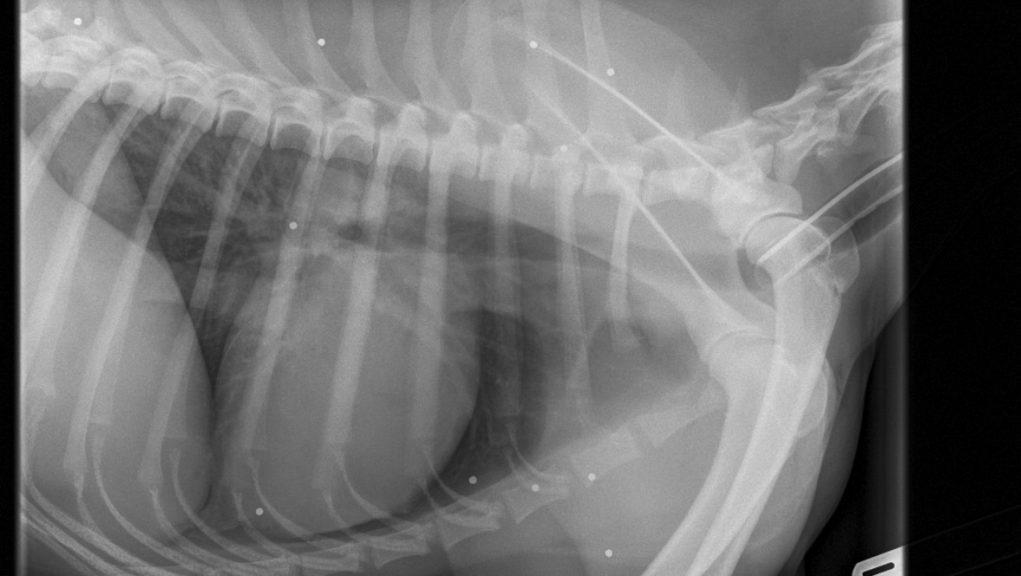

SHOTGUN INJURYDOG What Does A Pellet Gun Wound Look Like On A Dog Burns and dog‐bite wounds can be superficial or extensive, involving muscle, bone, and vital organs. In a healthy wound, fibroblasts and capillaries (small blood vessels) migrate into the area and create a framework for other cells to grow on. The pattern of dispersion can be changed by modifying the. If the number of intact bullets seen with imaging cannot be. What Does A Pellet Gun Wound Look Like On A Dog.